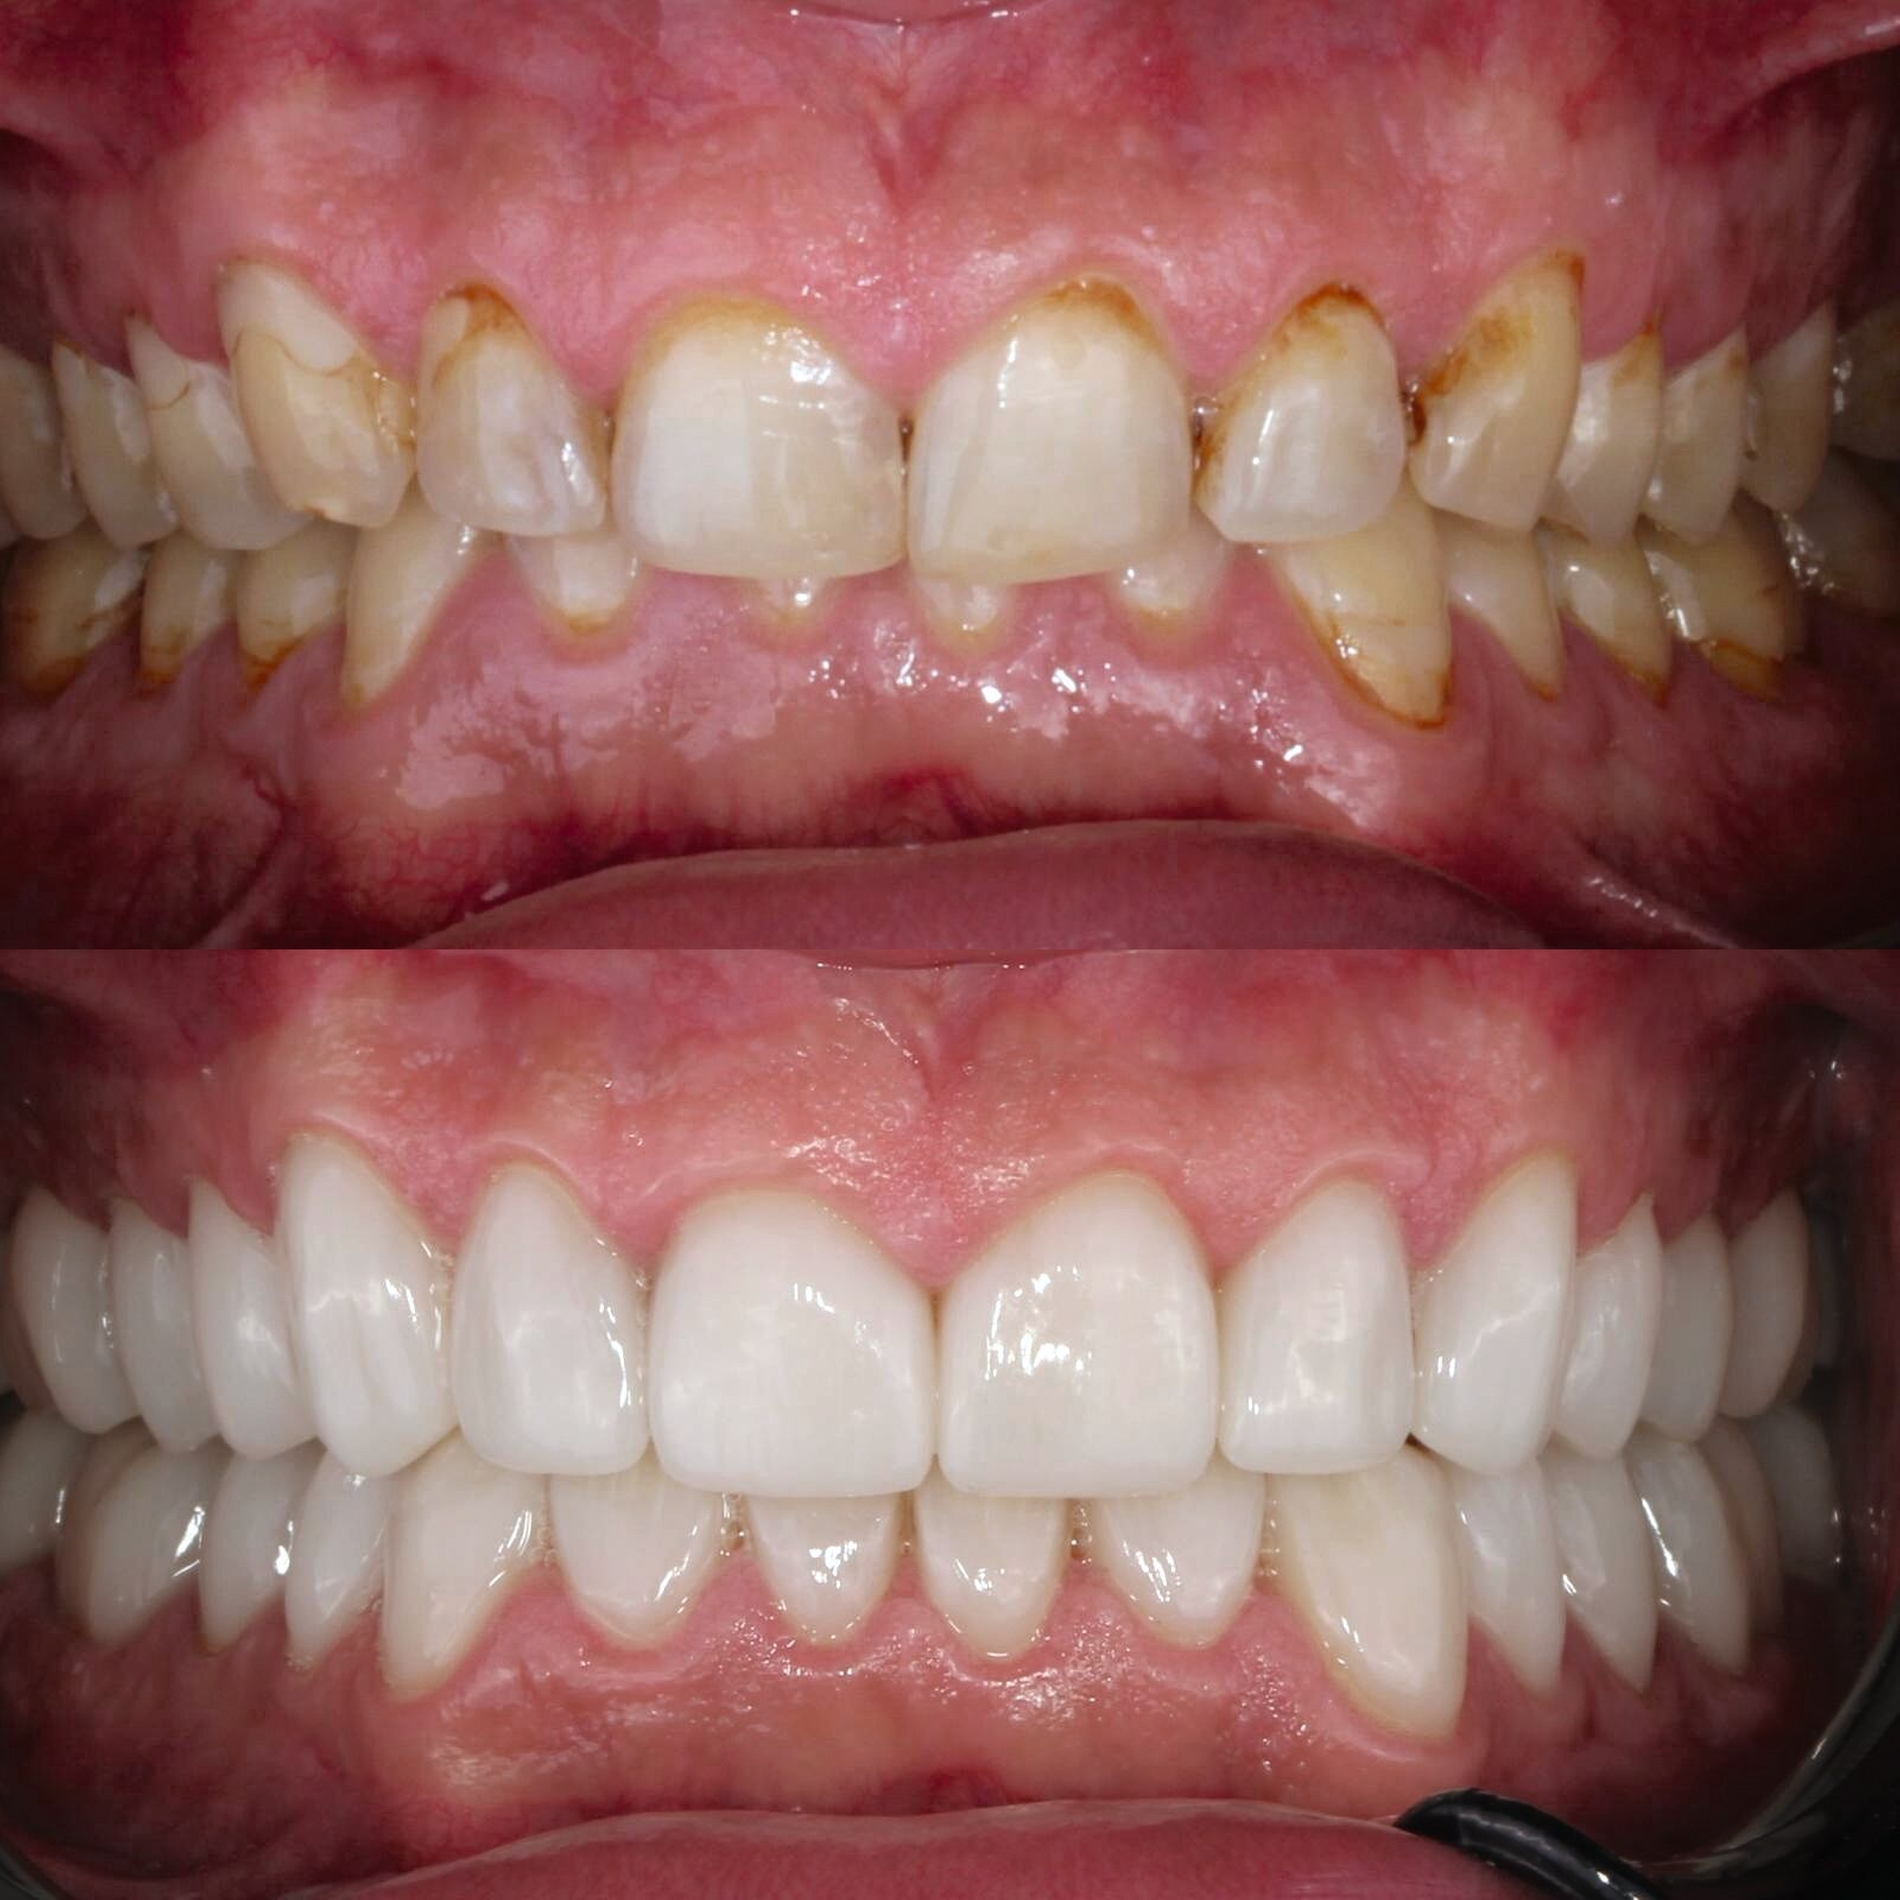

Klinisch präsentierte sich ein vollbezahntes Gebiss ohne Weisheitszähne mit Defekten an der Zahnstruktur teilweise bis ins Dentin. Es waren deutliche Erosionsspuren zu erkennen, die auf die säurehaltige Ernährung im Kurzzeitintervall zurückgeführt wurden. Der BEWE-Index war mit dem Wert 13 auffällig und kategorisierte den Schaden als ausgeprägte Erosionen. Die Zähne 14, 13 und 24 wiesen nicht-kariöse zervikale Defekte auf, diese treten häufig im Zusammenhang mit Bruxismus auf [Pecie et al., 2011]. Das CMD-Screening der Deutschen Gesellschaft für Funktionsdiagnostik und -therapie (DGFDT) [DGFDT, 2024] war unauffällig, da der Patient über keinerlei Schmerzen oder Beschwerden bei Kieferbewegungen klagte. Die manuelle Strukturanalyse (MSA) nach Bumann [Fasold und Kordaß, 2012] ergab bei diesem Patienten ein myofaziales Schmerzsyndrom. Im Prämolarenbereich imponierten Zahnhartsubstanzdefekte, die Hinweise auf starkes und häufiges Zähnepressen geben. Den Patienten selbst störten seine kälteempfindlichen Zähne sowie die Gesamtästhetik aufgrund des massiven Substanzverlustes.

Zu Beginn wurden mit Alginat Abformungen der Ausgangslage genommen. Anhand der Situationsmodelle konnten mithilfe einer Modellanalyse nach dem Udo-Plaster-Protokoll [Plaster und Köttgen, 2020] Rückschlüsse auf einen vertikalen Höhenverlust von etwa 3 - 4 mm gezogen werden. Für die Registrierung der neuen Höhe wurde der Patient mit einer temporären Einweg-Schiene (Aqualizer®, MediPlus GmbH, Unterleinleiter) deprogrammiert. Anschließend wurde am stehenden Patienten ein Bis-Acrylat-basierter Frontzahn-Jig (LuxaBite, DMG, Hamburg) angefertigt, so dass die Bissnahme als vorläufige patientenindividuelle Myozentrikposition reproduzierbar im Seitenzahnbereich mit einem A-Silikon (Kanibite hart, Kaniedenta, Herford) erfolgen konnte. Basierend auf dieser Höhe wurde eine Bisserhöhungsschiene angefertigt, die der Patient über sechs Monate lang trug. Nach einem Intraoralscan des Ober- und Unterkiefers (Primescan, Dentsply Sirona, Bensheim) konnte ein digitales Wax-up erstellt werden. Auf den 3-D-gedruckten Wax-up-Modellen wurde ein Silikonschlüssel für die Mock-up-Versorgung hergestellt und mit einem Bis-Acrylat-Komposit (Luxatemp Star, DMG, Hamburg) umgesetzt.

Da der Patient mit der Situation zufrieden war, konnte nach einigen Wochen die endgültige Versorgung bestehend aus Lithiumdisilikat-Kronen (e.max®, Ivoclar, Schaan, Liechtenstein) adhäsiv mit einem dualhärtenden Befestigungskomposit (RelyXUltimate™, 3M™, Neuss) eingesetzt werden. Der Patient bekam außerdem eine Unterkiefer-Aufbissschiene mit adjustierter Kaufläche für die Nacht.

Der Patient konnte vollständig saniert werden und kam mit der neu eingestellten Bisshöhe sehr gut zurecht. Während der Behandlung wurden Ernährungshinweise gegeben, um die langfristige Haltbarkeit der Restauration zu gewährleisten. Eine besondere Herausforderung stellten in diesem Fall der angestrebte Ausgleich der verlorenen vertikalen Höhe und die Bestimmung der Myozentrikposition dar.